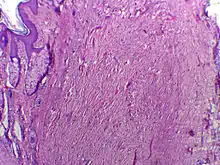

Une chéloïde, ou cicatrice chéloïdienne, est une forme de cicatrice résultant d’une excroissance du derme au niveau d’une blessure guérie. Elle se présente sous forme de lésions fermes, caoutchouteuses ou des nodules brillants, fibreux et sa couleur varie du rose au chair (pour les peaux claires) ou du rouge au brun foncé (pour les peaux foncées). Une cicatrice chéloïde est bénigne, non contagieuse et généralement accompagnée de fortes démangeaisons, voire de douleurs vives ; sa texture évolue dans le temps. Dans les cas les plus graves, elle peut affecter le mouvement de la peau.

Le processus de cicatrisation est caractérisé par un équilibre entre la synthèse et l’hydrolyse du collagène. Pendant la phase de prolifération, le taux d’apport en collagène dépasse celui de sa lyse. Puis apport et lyse s’équilibrent au cours de la phase de maturation. À cette étape, le collagène structurel de la cicatrice formée est réorganisé par l’action conjointe de la lyse et de la synthèse, aboutissant à une cicatrice mature.

Dans le cas des cicatrices chéloïdes et hypertrophiques, le point d’équilibre, généralement atteint 3 à 4 semaines après la blessure, n’est jamais atteint. L’apport de collagène reste supérieur à sa lyse pour une période indéfinie, provoquant une boursouflure au niveau de la cicatrice[1].

La cicatrice chéloïdienne poursuivra indéfiniment sa croissance à la fois en épaississant, et en s’étendant. Au contraire, une cicatrice hypertrophique ne se développe pas au-delà des limites de la blessure originale. Elle se stabilise puis se résorbe spontanément 2 à 3 ans après la blessure.